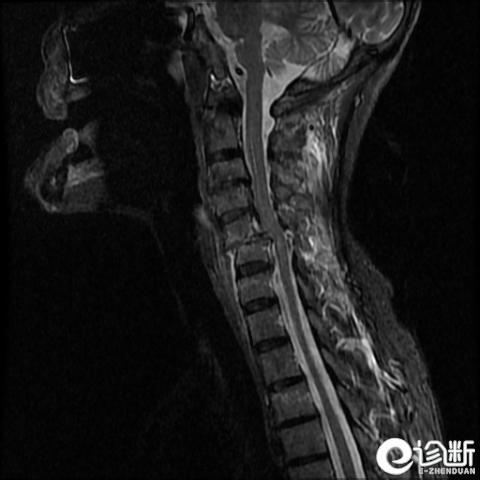

颈椎骨折

MRI:评估软组织

治疗:

所有骨折均应制动;牵引用于不稳定的下颈椎骨折

C1及C2:

稳定骨折:颈托或Halo环

不稳定骨折:Halo制动3个月和/或融合

2型齿突骨折:切开复位内固定(牵引加重病情)

C3-7:

稳定骨折:颈托或Halo

不稳定骨折:融合

棘突骨折:对症处理

并发症:神经损伤(如C1骨折可造成第11对脑神经损伤)、残留疼痛、骨关节炎、骨折不愈合(特别是2型齿突骨折)